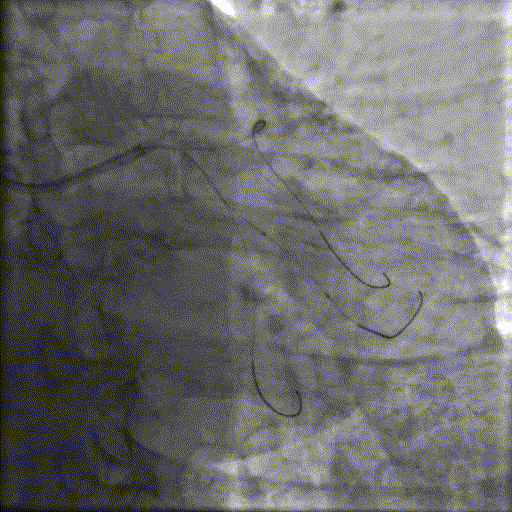

冲击波球囊治疗

2.5*12mm@4atm 冠脉血管内冲击波导管反复进行4个周期治疗,复查造影提示狭窄减轻。

支架植入并后扩

于OM2-LCX远端植入一枚药物洗脱支架,经非顺应性球囊后扩张支架,复查造影提示支架贴壁良好,未见夹层、血肿。